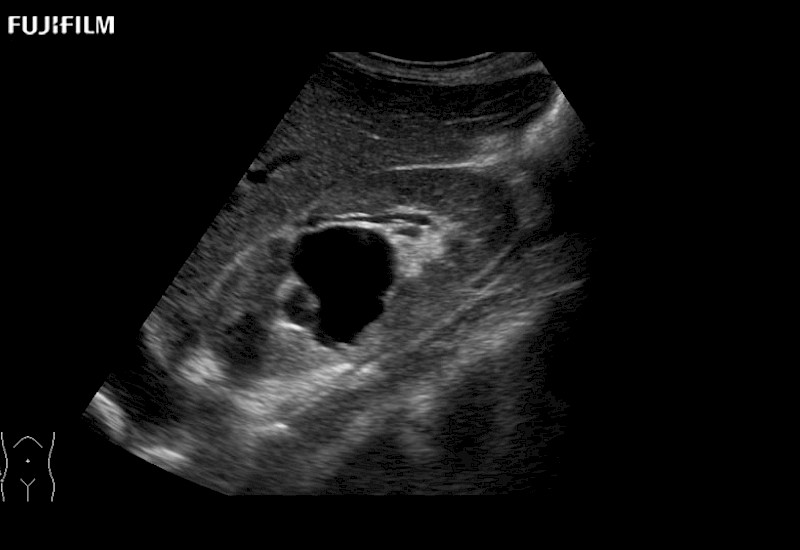

for use during open and laparoscopic procedures: Tumor localization & staging, Ablation, Resection, Biopsy, Transplant, Abdominal exploration, Robotic surgery

Our dedication to Surgical Oncology allows us to offer superior image quality, outstanding system reliability and intuitive use of cutting edge technology.